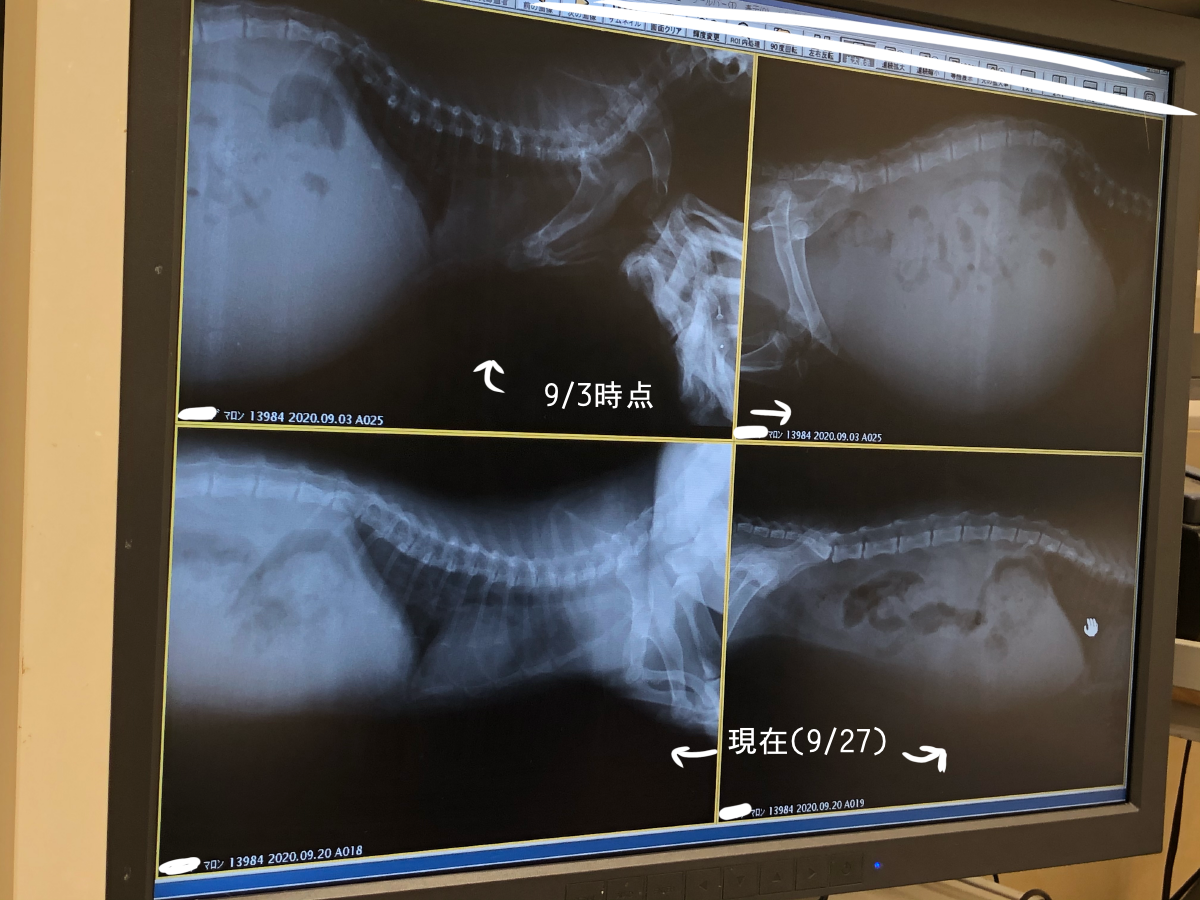

また、エコー検査でのマロンの写真がこちらになります。

マロンは現在順調に熱も下がり、食欲・元気両方回復してきています。84日間の投薬スケジュールは今のところ問題なく進んでいます。

上記を差し引いた金額すべて、マロンのFIP治療に関わる投薬費用・動物病院での定期的な診察代及び治療費・検査費(レントゲン、エコー、血液検査など)に、使わせていただきたいと思います。